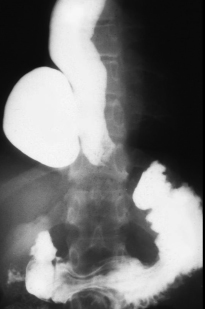

A etat tardive oesophage dilate et

alonge en forme de petit chaussette . |

Image radiologique une DES . Les

spasme de owsophage le plus souvent situe au portion

inferieure de oesophage. Bord irregulie et spastique

de oesophage voyait si net le cliche de face |

Image radiologique une DES au

temps d'evacuation de baryte |